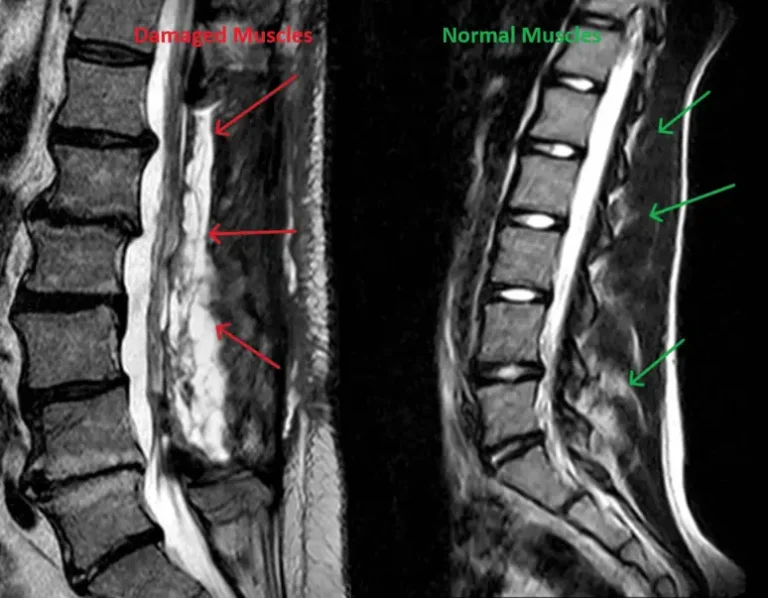

Laminectomy_Muscle_Damage

2) Destroys Spinal Muscles

Destruction of normal stabilizing bones including lamina and spinous process by the surgeon during laminectomy.